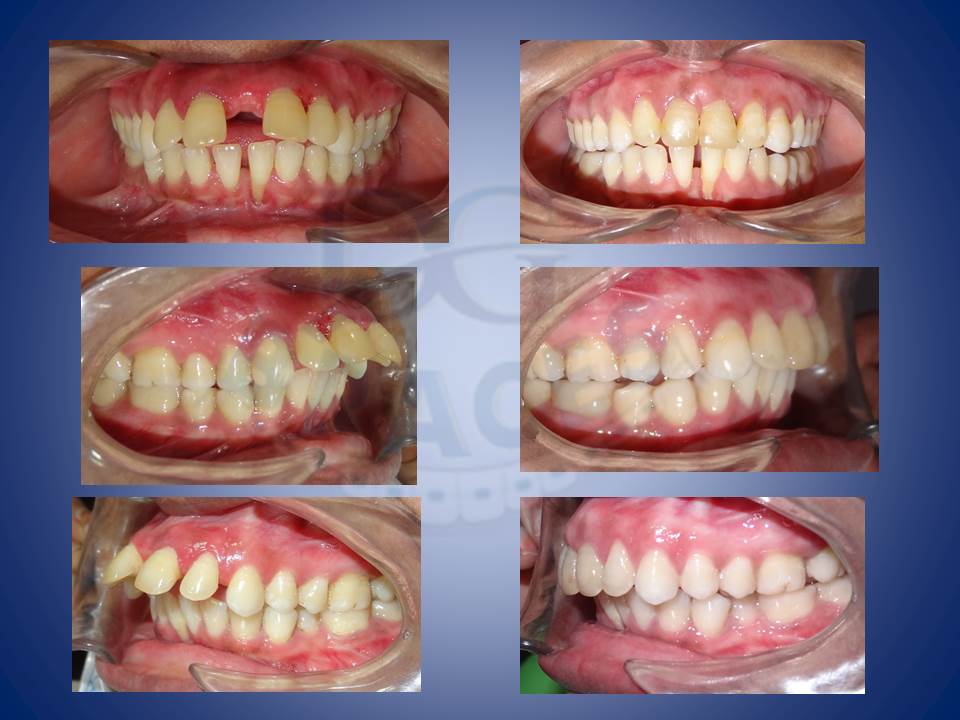

1.Crooked teeth are most often something which patients feel the need to be corrected. This is how we do it!!!